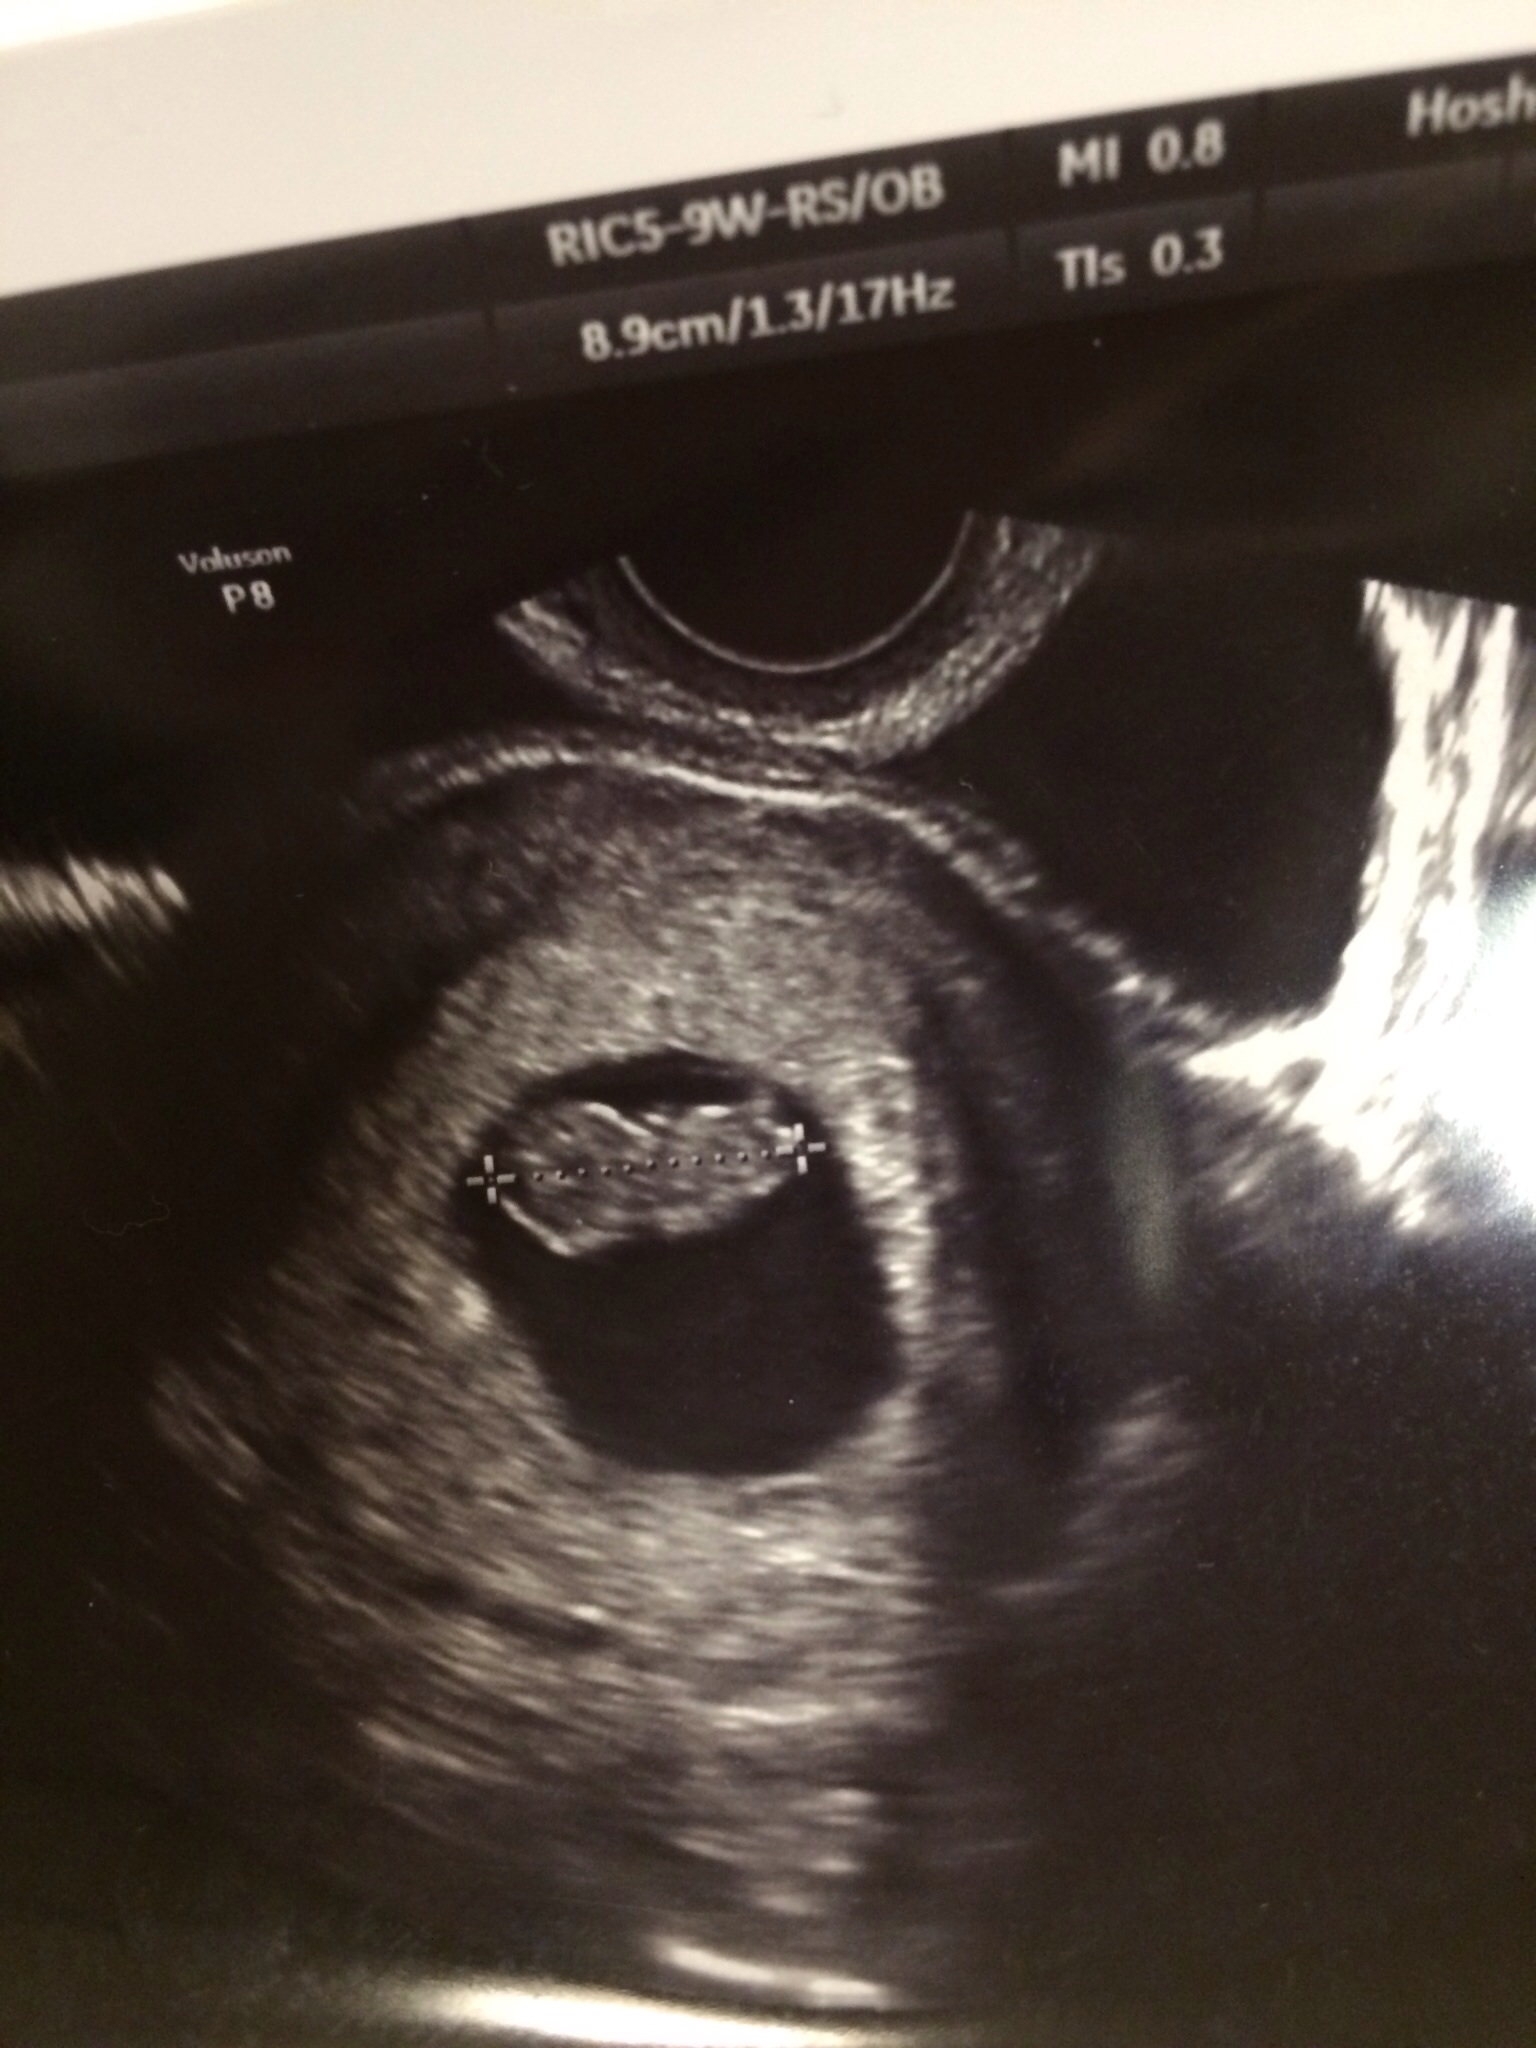

まず、初めて産婦人科に行ったときのことです。

妊娠検査薬で陽性と出ていたものの、

本当にできているのかどうかハラハラドキドキしながら行って、

お医者さんにお腹の中をカメラで見てもらい

第一声に言われたこと。

「これが心臓ですねー」

「えっ!!」

「こっちが頭でこっちがお尻です。」

「え!」

「妊娠3ヶ月くらいですね」

なんとか堪えましたが、思わずその場で涙が出そうになりました。

初めての赤ちゃんの映像

その時の衝撃は一生忘れないと思います。